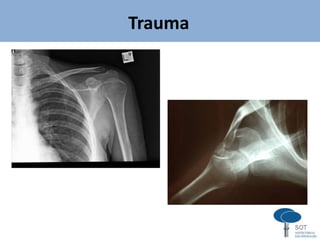

FRATURAS E LUXAÇÕES DA CINTURA ESCAPULAR

Trauma

Trauma - clavícula

CLAVÍCULA